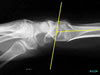

Aralıklı,belirli bir noktadan uzakta.